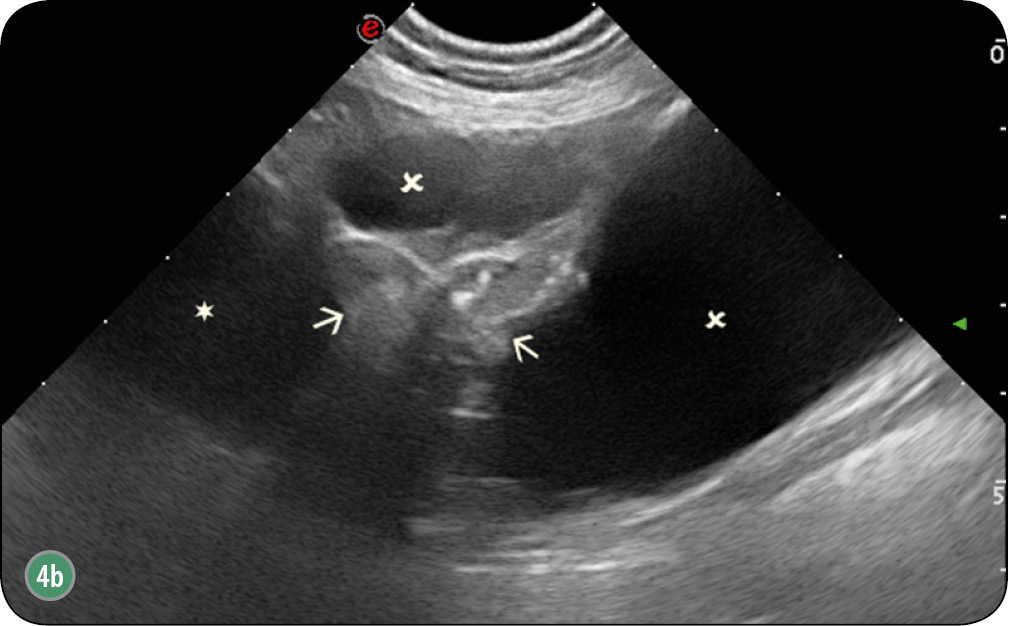

W obrazie ultrasonograficznym zmienionego nowotworowo gruczołu krokowego może wystąpić wiele zmian. Gruczoł zwykle ulega znacznemu powiększeniu, utkanie miąższu bywa często niejednorodne (ryc. 8), występują hiper- i hipoechogeniczne obszary (ryc. 9) (1, 4, 7, 12, 16, 21, 26, 30). Obserwuje się również zmiany jamiste o szorstkich krawędziach, zmiany lite o utkaniu tkankowym, jedno- lub wieloogniskowe (ryc. 4b). Nierzadko widoczne są hiperechogenne echa z cieniem akustycznym, które świadczą o obecności zwapnień (ryc. 10).